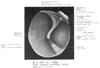

前ツチ骨ヒダ【ぜんつちこつひだ】 Fold on the inner surface of the tympanic membrane that extends anteriorly with a concave inferior border from the base of the handle of malleus.(鼓膜内側のヒダ。下方へはくぼみをなしてのび、前方へはツチ骨柄の根元からのびる。 (Feneis) TAの代用語ではAnterior maleolar foldとなっているがAnterior mallear foldが適当なので併記してある。)

Band2(654)